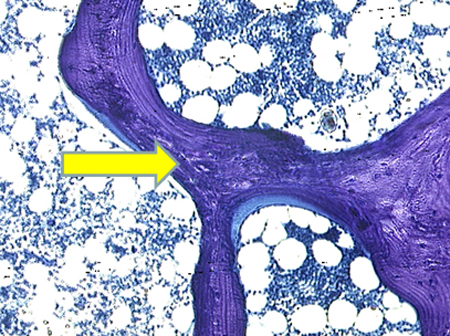

Osteomalácia

Fotomicrografia de biópsia óssea transilíaca normal demonstrando osteoide mineralizado (mostrado em roxo)

Do acervo de Bridget Sinnott, MD; usado com permissão